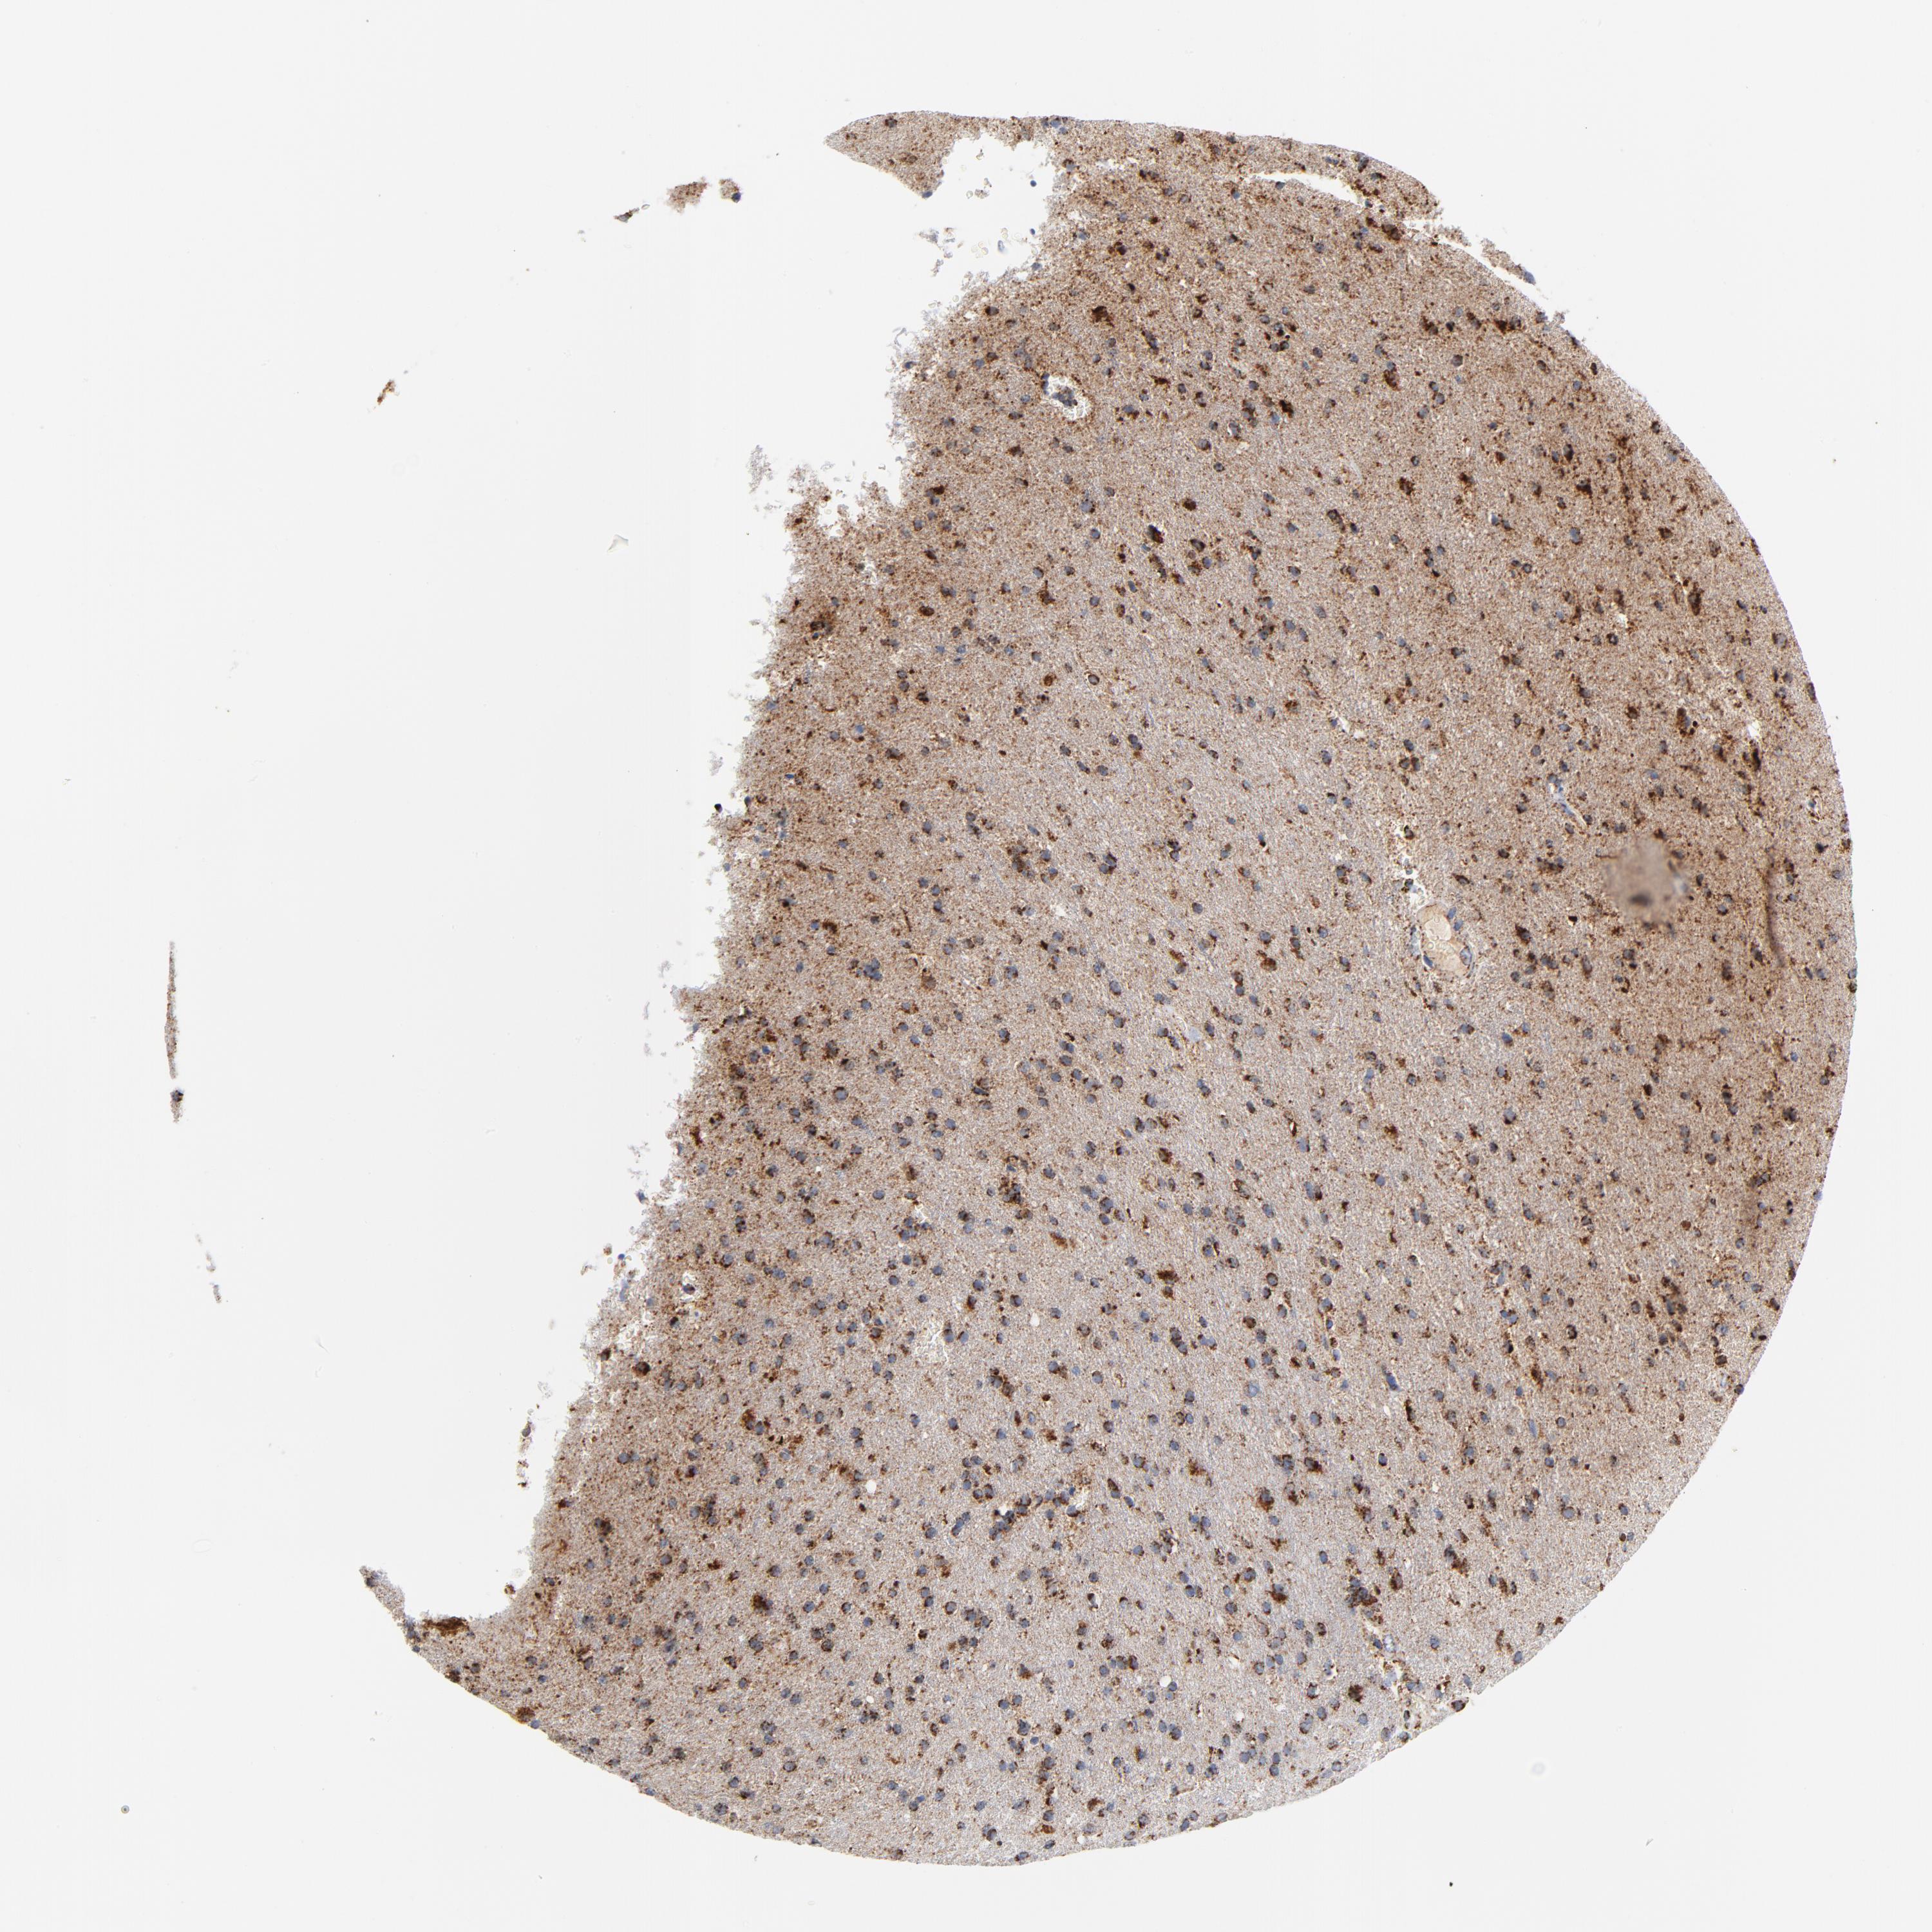

GLIOMA - Protein expressioni

A mouse-over function shows sample information and annotation data. Click on an image to view it in a full screen mode. Samples can be filtered based on level of antibody staining by selecting one or several of the following categories: high, medium, low and not detected. The assay and annotation is described here.

Note that samples used for immunohistochemistry by the Human Protein Atlas do not correspond to samples in the TCGA dataset.

Antibody stainingi

Antibody staining in the annotated cell types in the current human tissue is reported as not detected, low, medium, or high, based on conventional immunohistochemistry profiling in selected tissues. This score is based on the combination of the staining intensity and fraction of stained cells.

Each image is clickable and will lead to virtual microscopy that enables deeper exploration of all samples and also displays staining intensity scores, fraction scores and subcellular localization as well as patient and tissue information for each sample.

Antibody HPA001825

Antibody CAB003857

Staining

High

Medium

Low

Not detected

Intensity

Strong

Moderate

Weak

Negative

Quantity

>75%

75%-25%

<25%

None

Location

Nuclear

Cytoplasmic/membranous

Cytoplasmic/membranous,nuclear

Glioma, malignant, High grade

Glioma, malignant, Low grade

Glioma, malignant, NOS